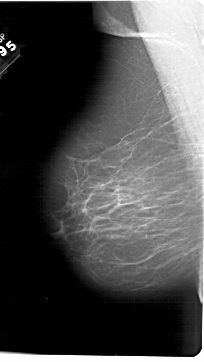

A_1765_1.LEFT_MLO

LEFT_MLO LINES 6871 PIXELS_PER_LINE 3871 BITS_PER_PIXEL 12 RESOLUTION 43.5 NON_OVERLAY